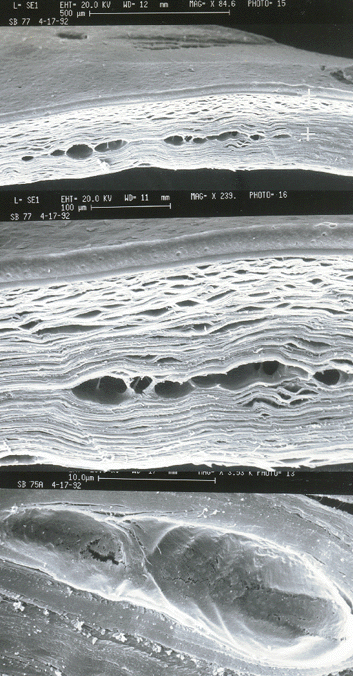

Cataract Fragmentation and Intrastromal Incisions.

Traversal cuts of the cornea after laser treatment.